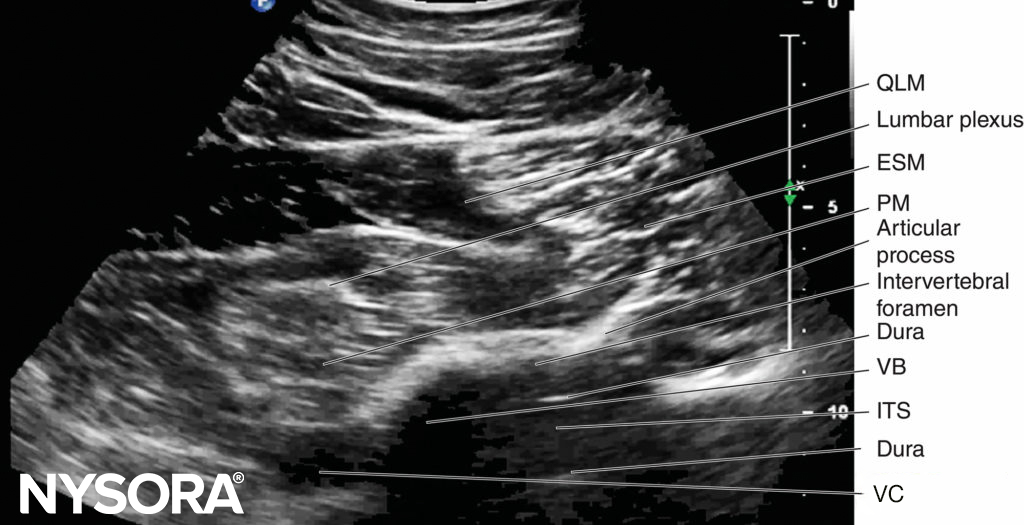

In contrast, during a PMTOS through the lumbar intertransverse space and at the level of the articular process (PMTOS-AP) (see Figure 10c), apart from the erector spinae, psoas, and quadratus lumborum muscles, the intervertebral foramen, articular process, and lumbar nerve root are clearly delineated (see Figure 14). The LPVS is also seen as a hypoechoic space adjacent to the intervertebral foramen (see Figure 14), and the lumbar nerve root can be seen exiting the foramen to enter the paravertebral space (see Figure 14).

After it exits the intervertebral foramen, the lumbar nerve root does not enter the psoas muscle directly opposite the intervertebral foramen from which it emerges (see Figure 14), but takes a steep caudal course (see Figure 14), entering the psoas muscle at the vertebral level below to join the lumbar plexus. The lumbar plexus is seen as a separate hyperechoic structure within a hypoechoic space, the psoas compartment, in the posterior aspect of the psoas muscle (see Figure 14). In a transverse sonogram produced by the shamrock method (see Figure 15), the psoas, erector spinae, and quadratus lumborum muscles are also clearly visualized (see Figures 16, 17, 18 and 19). The anatomical arrangement of the three muscles around the transverse process—that is, the psoas muscle lying anteriorly, the erector spinae muscle lying posteriorly, and the quadratus lumborum muscle lying at the apex (see Figure 16)—produces a sonographic pattern that has been likened to the shape of a “shamrock,” with the muscles representing its three leaves. The lumbar nerve root may also be visualized close to the angle between the vertebral body and the transverse process (see Figure 16) and the lumbar plexus within the posterior aspect of the psoas muscle, typically about 2 cm anterior to the transverse process (see Figures 17 and 18). From this position, if the transducer is gently tilted caudally, the acoustic shadow of the L4 transverse process disappears, and the US beam is now insonated through the intertransverse space and at the level of the articular process of the L4 vertebra, similar to that seen with a PMTOS-AP (see Figure 17). As a result, apart from the psoas, erector spinae, and quadratus lumborum muscles, the intervertebral foramen and lumbar plexus may also be visualized (see Figure 17).